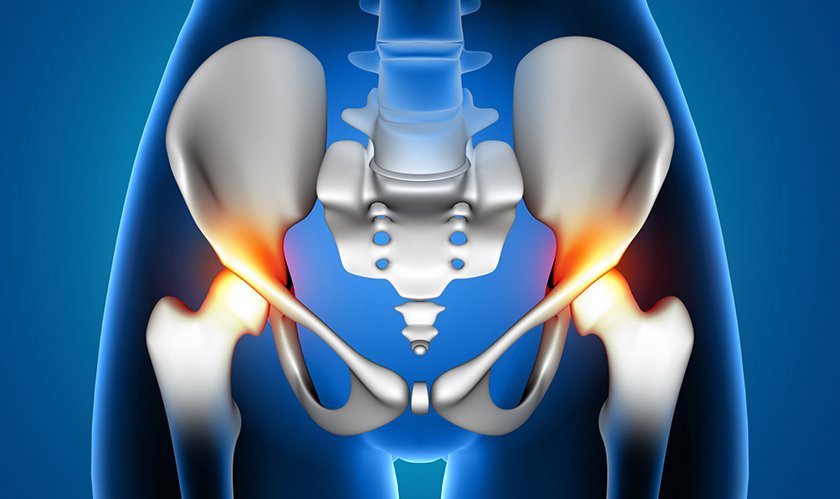

Advanced Hip Replacement for Pain Relief and Improved Mobility : Total Hip Replacement (THR) is a highly successful surgical procedure that relieves chronic hip pain, restores joint function, and improves overall quality of life. It is commonly recommended for patients with severe hip arthritis, hip joint damage, or fractures who have not found relief through non-surgical treatments..

Total hip replacement, also known as hip arthroplasty, involves removing the damaged portions of the hip joint and replacing them with an artificial implant. The damaged hip socket is fitted with a prosthetic cup, and the femoral head is replaced with a metal or ceramic ball attached to a stem, allowing smooth and pain-free movement.

Hip joint damage due to arthritis, injury, or avascular necrosis